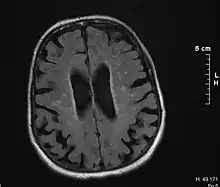

Binswanger's disease can usually be diagnosed with a CT scan, magnetic resonance imaging, and proton magnetic resonance spectrography in addition to clinical examination. Indications include infarctions, lesions, or loss of intensity of central white matter and enlargement of ventricles, and leukoaraiosis. A mini–mental state examination has been created to quickly assess cognitive impairment and serves as a screening test for dementia across different cultures.[13]

Leukoaraiosis refers to the imaging finding of white matter changes that are common in Binswanger disease. However, leukoaraiosis can be found in many different diseases and even in normal patients, especially in people older than 65 years of age.[5]

There is controversy whether leukoaraiosis and mental deterioration actually have a cause and effect relationship. Research has shown that different types of leukoaraiosis can affect the brain differently, and that proton magnetic resonance spectroscopy would be able to distinguish the different types more effectively and better diagnose and treat the issue.[9] Because of this information, white matter changes indicated by magnetic resonance imaging or computerized tomography cannot alone diagnose Binswanger disease, but can aid to a bigger picture in the diagnostic process. There are many diseases similar to Binswanger's disease including CADASIL syndrome and Alzheimer's disease, which makes this specific type of white matter damage hard to diagnose.[5] Binswanger disease may be diagnosed by a team of experts including a neurologist and psychiatrist to rule out other psychological or neurological problems.[3]

Much of the major research today is done on finding better and more efficient ways to diagnose this disease. Many researchers have divided the magnetic resonance imaging of the brain into different sections or quadrants. A score is given to each section depending on how severe the white matter atrophy or leukoaraiosis is. Research has shown that the higher these scores, the more of a decrease in processing speed, executive functions, and motor learning tasks.[14][15] Other researchers have begun using computers to calculate the percentage of white matter atrophy by counting the hyper-intense pixels of the magnetic resonance images. These and similar reports show a correlation between the amount of white matter alterations and the decline of psychomotor functions, reduced performance on attention and executive control.[16][17] One type of technology is called susceptibility weighted imaging (SWI) which is a magnetic resonance technique which has an unusually high degree of sensitivity and can better detect white matter alterations.[18]